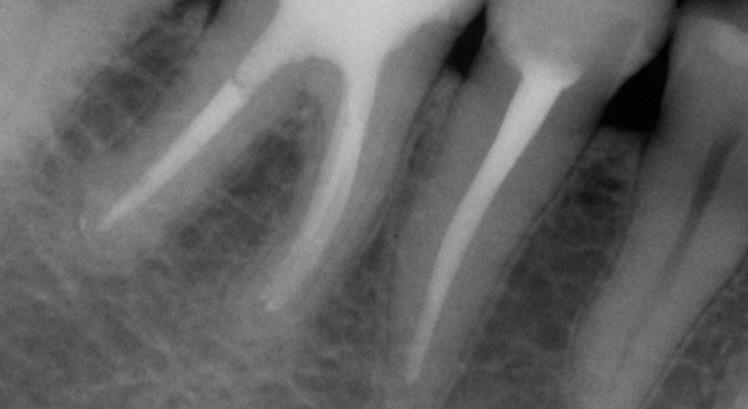

Even when the endodontic treatment is finished with an indirect restoration (a crown, onlay or overlay), FRC can be used for core build-ups such as a Nayyar’s core. This will be mostly indicated in retreatment cases, where the orifice part of the canal had already been prepared (Figs. 9-13).

Fig. 9: Pre-operative X-ray.

Fig. 12: Final X-ray.

Fig. 10: Cavity before placement of everX Posterior (GC), a fibre-reinforced composite in paste consistency.